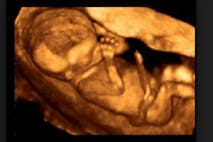

A pastor answers: When is a baby a baby?